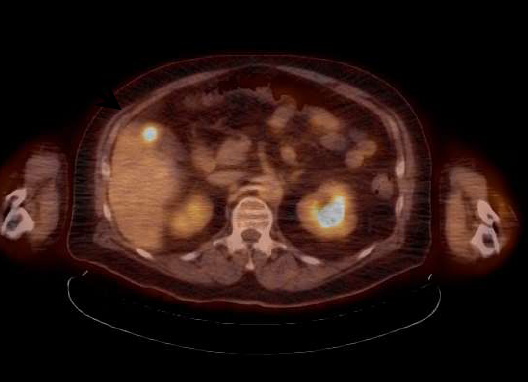

Positron emission tomography (PET) has become a standard of care in cancer patient management. Fluorine-18 fluorodeoxyglucose (F-18 FDG) is a radiotracer that closely resembles the metabolic activity of glucose in cells throughout the body. F-18 FDG emits a signal that is detected by the PET scanner. Image reconstructions of these signals let clinicians know where there are areas of abnormally increased metabolic activity, quantified by standardized uptake values (SUV). Accurate tumor SUVs enable clinicians to assess disease progression, reflected by an increased SUV; stable disease, reflected by no significant changes in SUV; and successful response to therapy, reflected by a decrease in SUV.

Radiotracer tumor SUVs are quantitatively measured using patient weight. However, F-18 FDG is distributed almost exclusively in LBM, not fatty tissue. Current methods of SUV normalization tend to focus on overall weight and may significantly over- or underestimate LBM in cancer patients. For this study, researchers developed a computed tomography (CT) technique that determines patient-specific LBM. This method of SUV normalization, using patient-specific LBM, is termed SULps.

Researchers analyzed CT scans in three-month intervals to gauge changes in body composition of patients with advanced cancer. A total of 1,080 intervals of CT were evaluated and just over 50 percent, or 546 intervals, reflected stable LBM. Of this smaller group with stable LBM, 40 percent experienced a decrease in adipose tissue, 35 percent showed no change in adipose tissue, and 25 percent showed an increase in adipose tissue. These changes affect SUV using all calculations except SULps, which accurately reflected metabolic activity via F-18 FDG PET/CT.